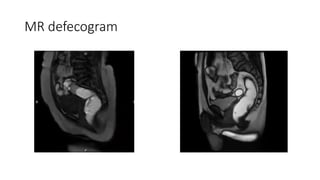

(A-D): Normal MR defecogram. Normal position of the anorectal junction ...